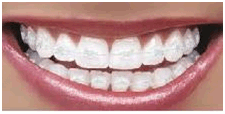

Orthodontic irregularities are generally treated with braces. Braces are usually made from wires and springs attached to tiny metal plates or a plastic mould. Braces apply gentle forces to teeth and encourage them to to move slowly to adopt a different alignment. The best orthodontic results are achieved with children when their teeth are still growing; many adults have orthodontic treatment, but the process takes much longer. Visit our main braces page to read more about how they work and how to look after them.

The orthodontist will assess the teeth that need to be aligned and create either a fixed or removable brace, which can be adjusted during the course of the treatment to achieve the desired effect. The fixed braces, as their name implies, are permanent fixtures and are removed at the end of the treatment period, whereas removable braces can be taken off for eating and cleaning but are generally worn at all other times. Braces will improve the function of the teeth and the general appearance of the person.